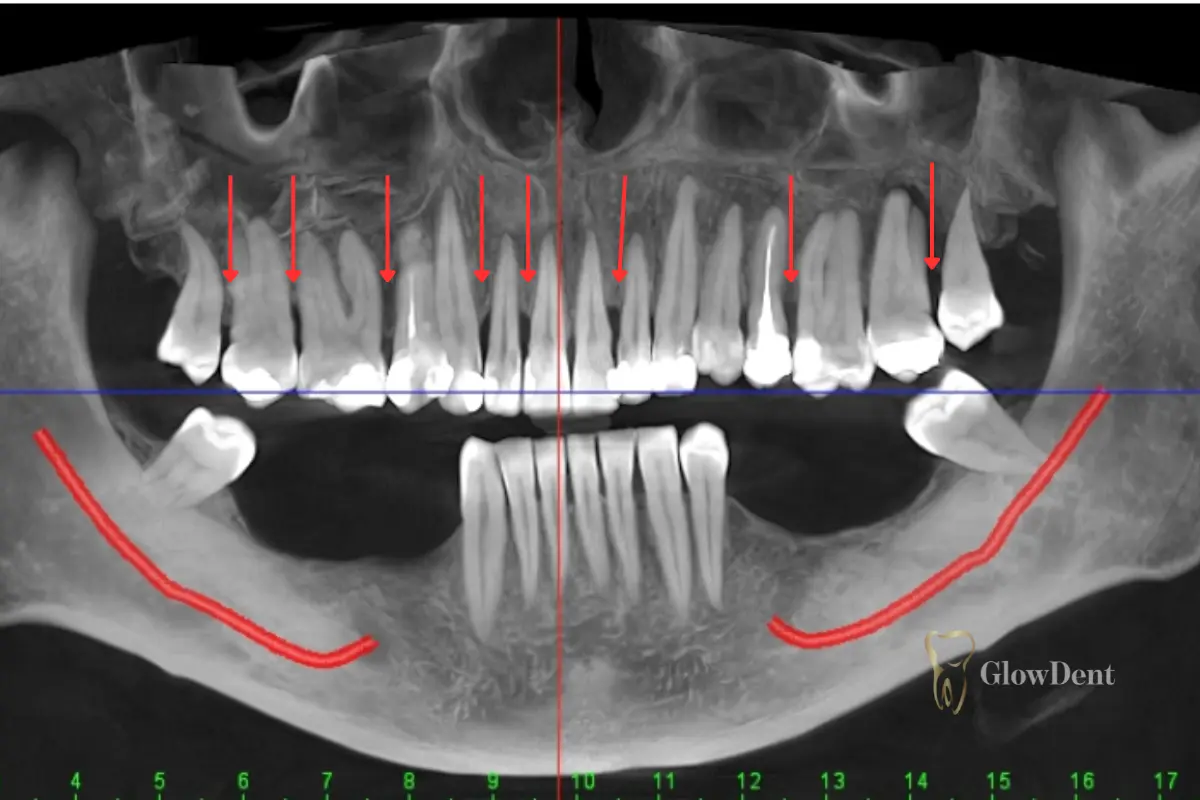

Parodontitis, auch bekannt als Parodontalerkrankung, ist eine chronische Erkrankung, die das Stützgewebe der Zähne betrifft. Sie beginnt mit milden Symptomen wie Zahnfleischbluten beim Zähneputzen, Empfindlichkeit und Mundgeruch. Mit der Zeit zieht sich das Zahnfleisch zurück, wodurch die Zahnwurzeln freigelegt und empfindlich werden.

Wenn die Krankheit vernachlässigt wird, kann sie zum Verlust von Knochensubstanz und schließlich der Zähne führen. Daher ist eine rechtzeitige Behandlung der Parodontitis von entscheidender Bedeutung. Es ist auch wichtig zu verstehen, dass diese Krankheit nicht nur ältere Menschen betrifft – sie kann auch bei jüngeren Personen auftreten, insbesondere wenn eine genetische Veranlagung oder eine schlechte Mundhygiene vorliegt.